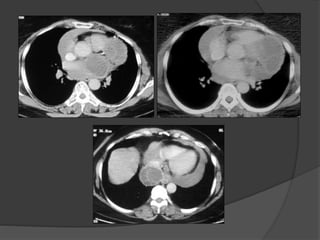

Case A 3:

73 year old male , R/O mass,

heart attack

Dx: Ruptured coronary graft pseudoaneurysm with

hemothorax

•Late complication of coronary bypass surgery

•Most aneurysms associated with saphenous

vein CABGs occur at the anastomotic sites.

Sutural defects, structural weakness of the

parent artery, deficiency in the preparation of

the saphenous vein and progressive

atherosclerosis

•Mediastinal or hilar mass on radiographs,

vascular nature of the mass on CECT or MRI,

extent and mass effect

•Complications of graft aneurysmal disease

are thrombosis, thromboembolism, fistula

formation to the right atrium or ventricle,

rupture and MI

Case A 3: 73year old male , R/O mass, heart attack

• 114.

Dx: Ruptured coronarygraft pseudoaneurysm with hemothorax •Late complication of coronary bypass surgery •Most aneurysms associated with saphenous vein CABGs occur at the anastomotic sites. Sutural defects, structural weakness of the parent artery, deficiency in the preparation of the saphenous vein and progressive atherosclerosis •Mediastinal or hilar mass on radiographs, vascular nature of the mass on CECT or MRI, extent and mass effect •Complications of graft aneurysmal disease are thrombosis, thromboembolism, fistula formation to the right atrium or ventricle, rupture and MI

• 116.